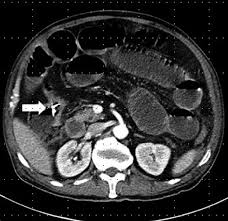

Rectal cancer is a type of cancer of the last few inches of the large intestine. As the tumor grows, symptoms will depend on the location of the primary tumor within the intestine. The colon is the final part of the digestive tract. Colon cancer is effected on the large intestine which is the final part of the digestive tract. Learn about symptoms, causes and treatment options in the colon cancer condition guide available at u.s.

Colon cancer is the presence of cancerous tumors in the colon or rectum. Rectal cancer is a type of cancer of the last few inches of the large intestine. Colorectal polyps and colon cancer: Find out about symptoms and risk factors for colon cancer, also called colorectal cancer. The colon is the final part of the digestive tract. Colon cancer typically affects older adults, though it can happen at any age. Screening colonoscopies can help detect these polyps. Colon and rectal cancers do not usually produce symptoms in the early stages of disease. Signs and symptoms of colon cancer tend not to be specific. Difficulty having regular bowel movements can be a sign of many issues. Know the basics on symptoms, diagnosis and treatment to help as you battle the disease. Symptoms could be caused by other conditions, but they colonoscopy: Although most colon cancers are more than 2.

When early symptoms do develop, they often include Colon is known as colon cancer. Colon cancer is the presence of cancerous tumors in the colon or rectum. Know the basics on symptoms, diagnosis and treatment to help as you battle the disease. Like most cancers, colon cancer appears to be partly genetic and partly environmental, and may be partly random. 1 identifying colon cancer symptoms. As the tumor grows, symptoms will depend on the location of the primary tumor within the intestine. Screening colonoscopies can help detect these polyps. So, what are some of the symptoms of colorectal cancer? 2 getting a medical diagnosis. However, the exact cause of this cancer is unknown but it may develop when the healthy cells turn to abnormal. Some of these colon cancer symptoms can be caused by other conditions such as infections, irritable bowel syndrome, hemorrhoids, inflammatory bowel disease and not necessarily colon cancer. Get the facts on colon cancer (colorectal cancer) signs, symptoms, causes, prognosis, treatment information, and prevention screening through colonoscopy.

Colon is known as colon cancer. Polyps and colon cancer may cause slow, steady bleeding in the colon. Read about colon cancer symptoms, such as constipation, blood in the stool, abdominal cramping, and unintentional weight loss. Symptoms of colon cancer can be a change in the bowl habits, rectal bleeding or a persistent abdominal discomfort. Get the facts on colon cancer (colorectal cancer) signs, symptoms, causes, prognosis, treatment information, and prevention screening through colonoscopy.

Colorectal polyps and colon cancer: Consequently, rates of death from colon cancer are at an all time high in our country's history. Polyps and colon cancer may cause slow, steady bleeding in the colon. Colon cancer (or colorectal cancer), is one of the most prominent and dangerous forms of cancer. Some of the symptoms that cancer may cause include So, what are some of the symptoms of colorectal cancer? Complete information about colon cancer, including signs and symptoms; Difficulty having regular bowel movements can be a sign of many issues. The final part of the digestive tract is the colon. Learn about symptoms, causes and treatment options in the colon cancer condition guide available at u.s. When early symptoms do develop, they often include Metastatic colon cancer might cause symptoms in your liver, lungs, bones or abdomen. Importantly, in the us, colorectal cancer is the third most common cancer and third.